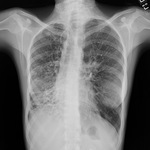

Chest x-ray showing hyperinflation in a patient with COPD. The hyperinflation is caused by the emphysema component of COPD, rather than the chronic bronchitis that underlies symptoms of cough

From the personal collection of Dr M. A. Sharifabadand, SUNY at Stony Brook School of Medicine, Department of Pulmonary and Critical Care Medicine, Mineola, New York and Dr J. P. Parsons, The Ohio State University Medical Center, Columbus; used with permission